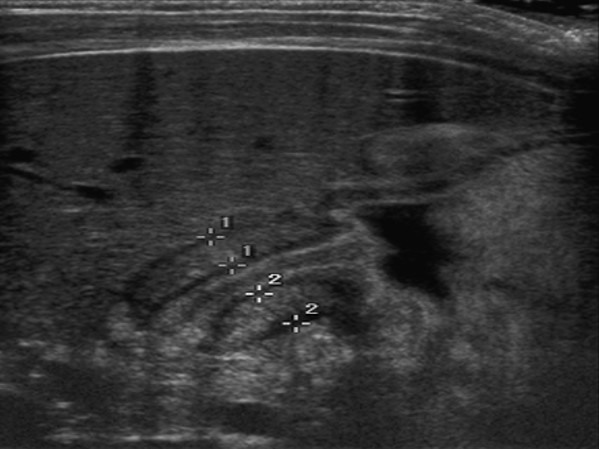

What is the modality of choice for diagnosis of pyloric stenosis?

Ultrasound (accurate muscle thickness and length measurements).

What are the upper GI radiographic findings for pyloric stenosis?

Delayed or absent gastric emptying; impression of enlarged pylorus on distal stomach.